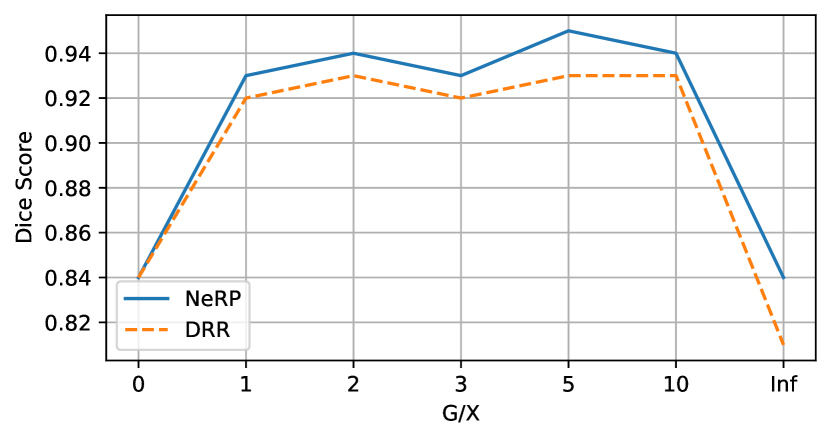

In this assessment, we gradually include portions of Chest XR with Lung annotation to train the U-Net and observe the performance over the quota of having extra annotated subsets of 2D XR data (see Fig. 4). Fig. 5 shows the Dice Scores on the separated test set for this setup. The horizontal axis represents the ratio (G/X) between the number of the generated images and XR images: means that the model was trained from XR only, and Inf means that model was trained from the generated images only. The results indicate that mixing the handful of annotated data with NeRP images yields better performance (up to 2%) over conventional DRR.